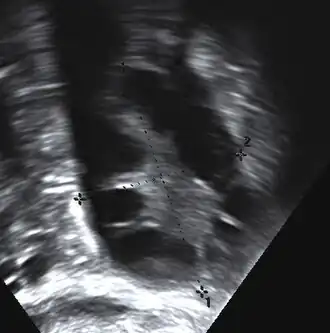

Gynecologic ultrasonography first looks for small ovarian follicles.[104] To count as polycystic ovaries, at least 20 follicles need to be present, smaller than 9 mm. This used to be 12 in older diagnostic criteria.[99] A less clear marker of PCOS is enlarged ovaries.[104] Ovary need to be at least 10 cm3 to count.[99] For sexually active individuals or those that agree, a transvaginal ultrasound approach is preferred. Alternatively, AMH levels can be tested in the blood.[104] Laparoscopic examination may reveal a thickened, smooth, pearl-white outer surface of the ovary. This would usually be an incidental finding if laparoscopy were performed for some other reason, as it would not be routine to examine the ovaries in this way to confirm a diagnosis of PCOS.[107]

-

Transvaginal ultrasound scan of polycystic ovary -

Polycystic ovary as seen on sonography